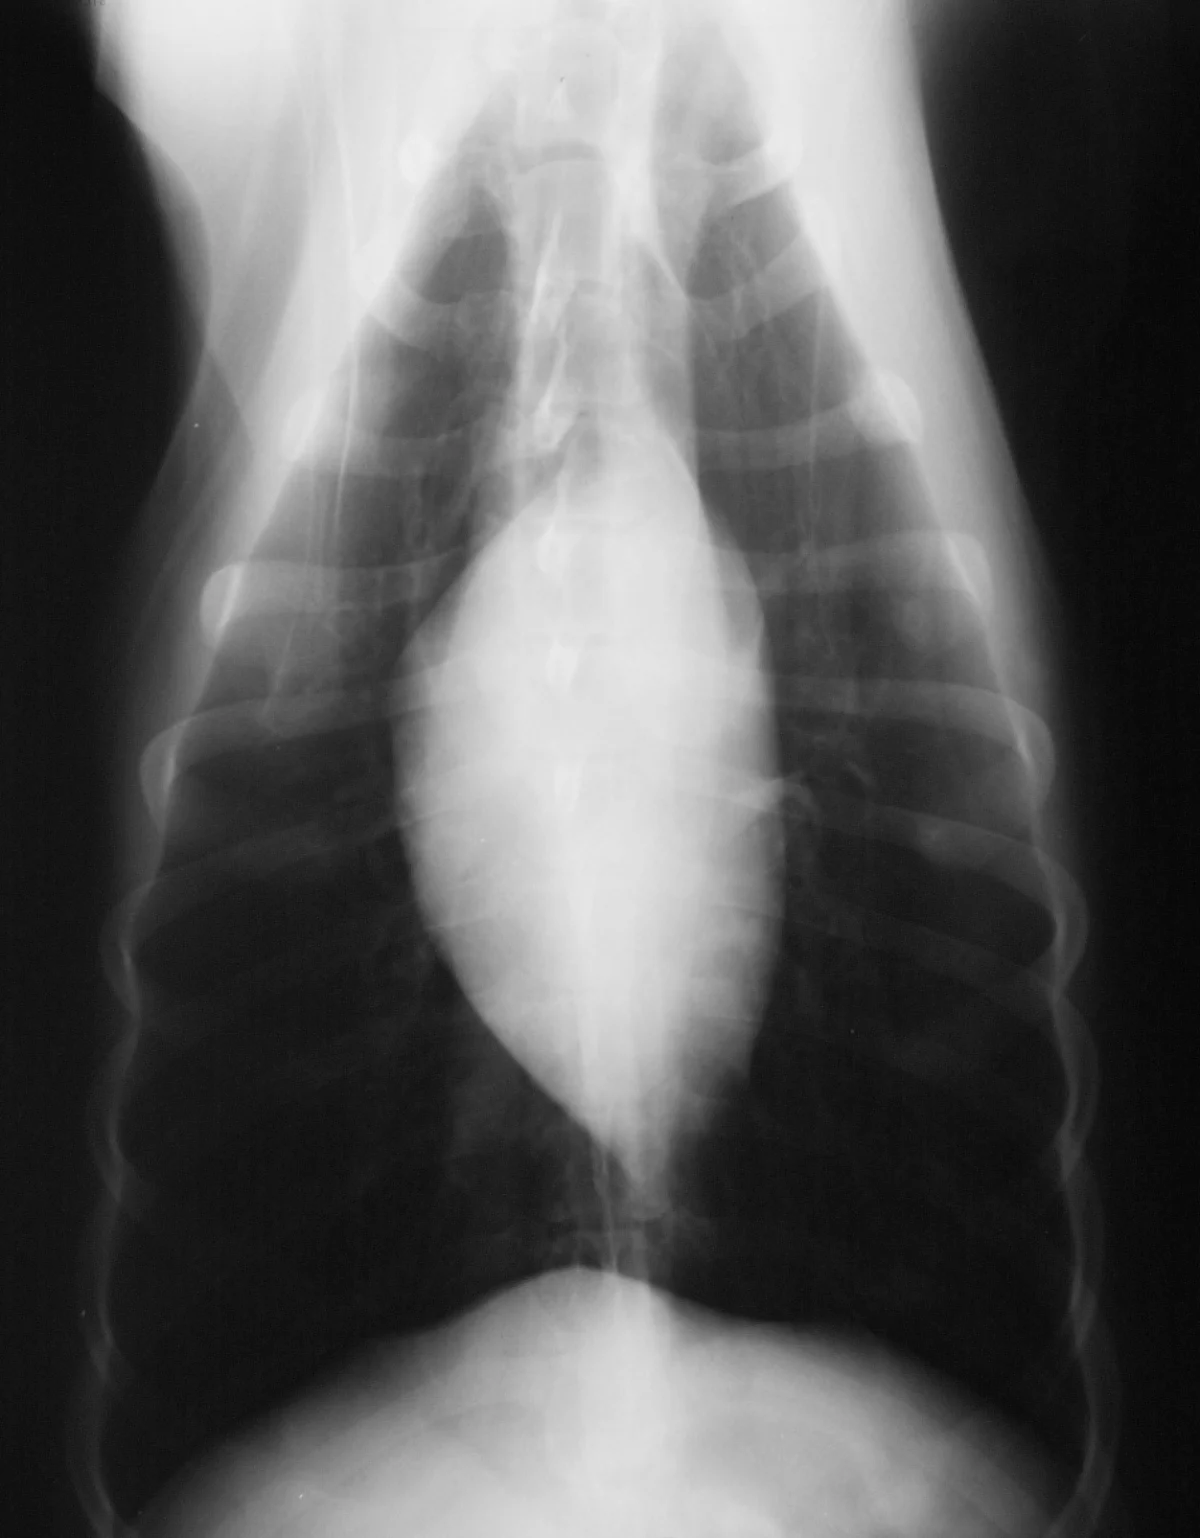

Thoracic radiograph from a dog with hypoadrenocorticism revealing microcardia. Microcardia is a nonspecific finding indicative of hypovolemia.